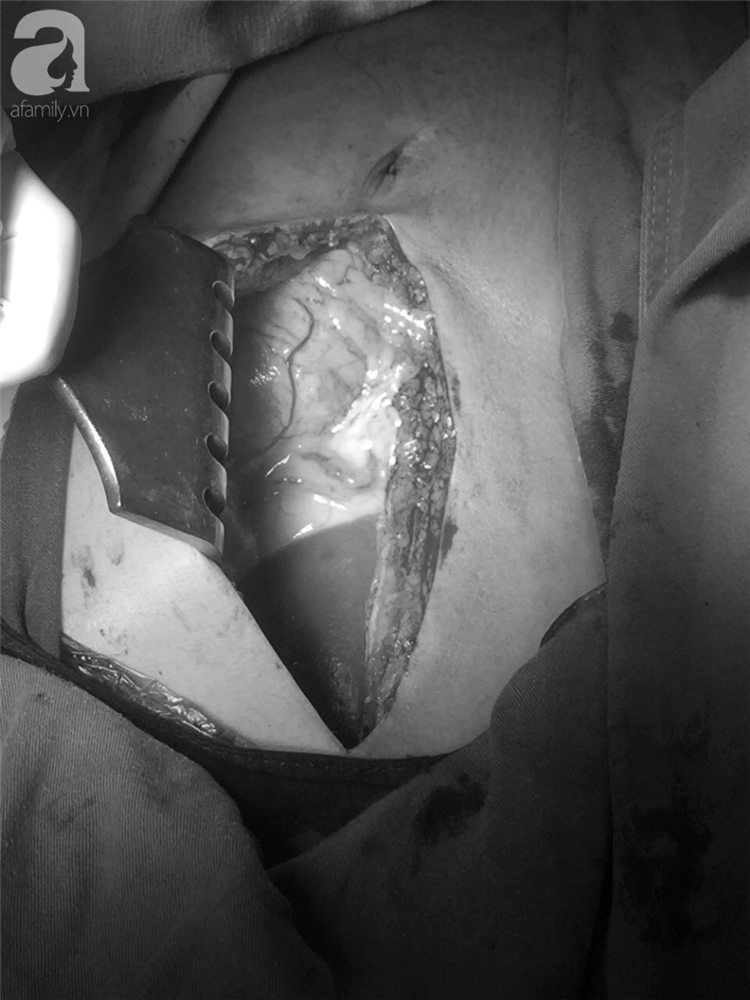

Vết thương do dao đâm gây thủng tim, phổi.

Bác sĩ Trương Trí Hữu, Phó Giám đốc BV CTCH TP HCM cho biết, bệnh nhân có 4 vết thương thấu ngực bằng kéo, vết thương gây thủng màng tim, rách cơ tim, vết thương tiếp theo bị thủng màng phổi, rách nhu mô phổi.